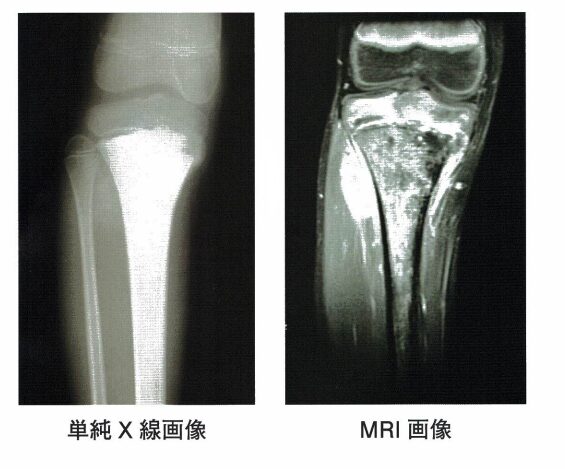

10 12歳の男児。約2か月来の膝関節痛を主訴に近医を受診した。陸上部に所属しているが、特に外傷の既往はない。下腿近位部の腫脹、圧痛、安静時痛を認めた。膝関節の可動域は疼痛のため、著明に制限されていた。単純Ⅹ線画像およびMRI画像を下に示す。画像所見で異常を指摘され、紹介受診となった。発熱はなく全身状態は良好。血液検査では炎症反応は正常で、ALPの上昇を認めた。

解答3

・12歳の男児(主訴:約2か月来の膝関節痛)。

・陸上部に所属(特に外傷の既往はない)。

・下腿近位部の腫脹、圧痛、安静時痛を認めた。

・膝関節の可動域は疼痛のため、著明に制限されていた。

・発熱はなく全身状態:良好。

・血液検査では炎症反応:正常、ALP:上昇。

3.〇 正しい。骨肉腫が最も考えられる疾患である。なぜなら、本症例の症状と合致するため。

・骨肉腫とは、腫瘍の細胞が骨の材料(類骨)を作って増える悪性腫瘍である。思春期に多く、膝の周り(太ももの骨の下端やすねの骨の上端)にできやすい。腫れや押すと痛い、じっとしていても痛い、関節が動かしにくいことがある。血液で骨を作る指標(ALP)が上がることがある。X線やMRIで骨の壊れや骨の膜の反応、骨の外へ広がるこぶ状のかたまりが見えやすい。